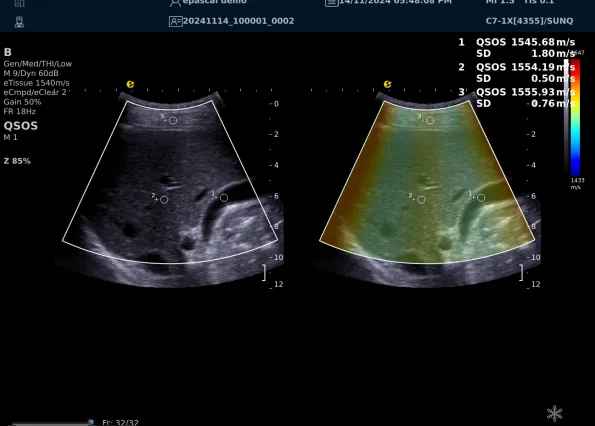

640.jpg123 (2).jpg可以设想,单位时间可发射的脉冲波越多、单位面积可发射的脉冲波越密集,得到的数据结果就越快、越多。也就是说,如果医生希望得到实时、大幅的声速定量图像,就需要超声系统具备“超快速”发射和接收的能力,hjc888黄金城官网医疗(ESI)ePascal东风系列超声平台的200+倍成像速度,成为了这项新技术得以临床应用的重要条件。

以上为应用声速定量成像技术检查肝脏的超声图像,图中在取样框内选择了三个测量区域,得出了各区域内的组织声速值以及声速衰减系数等结果。